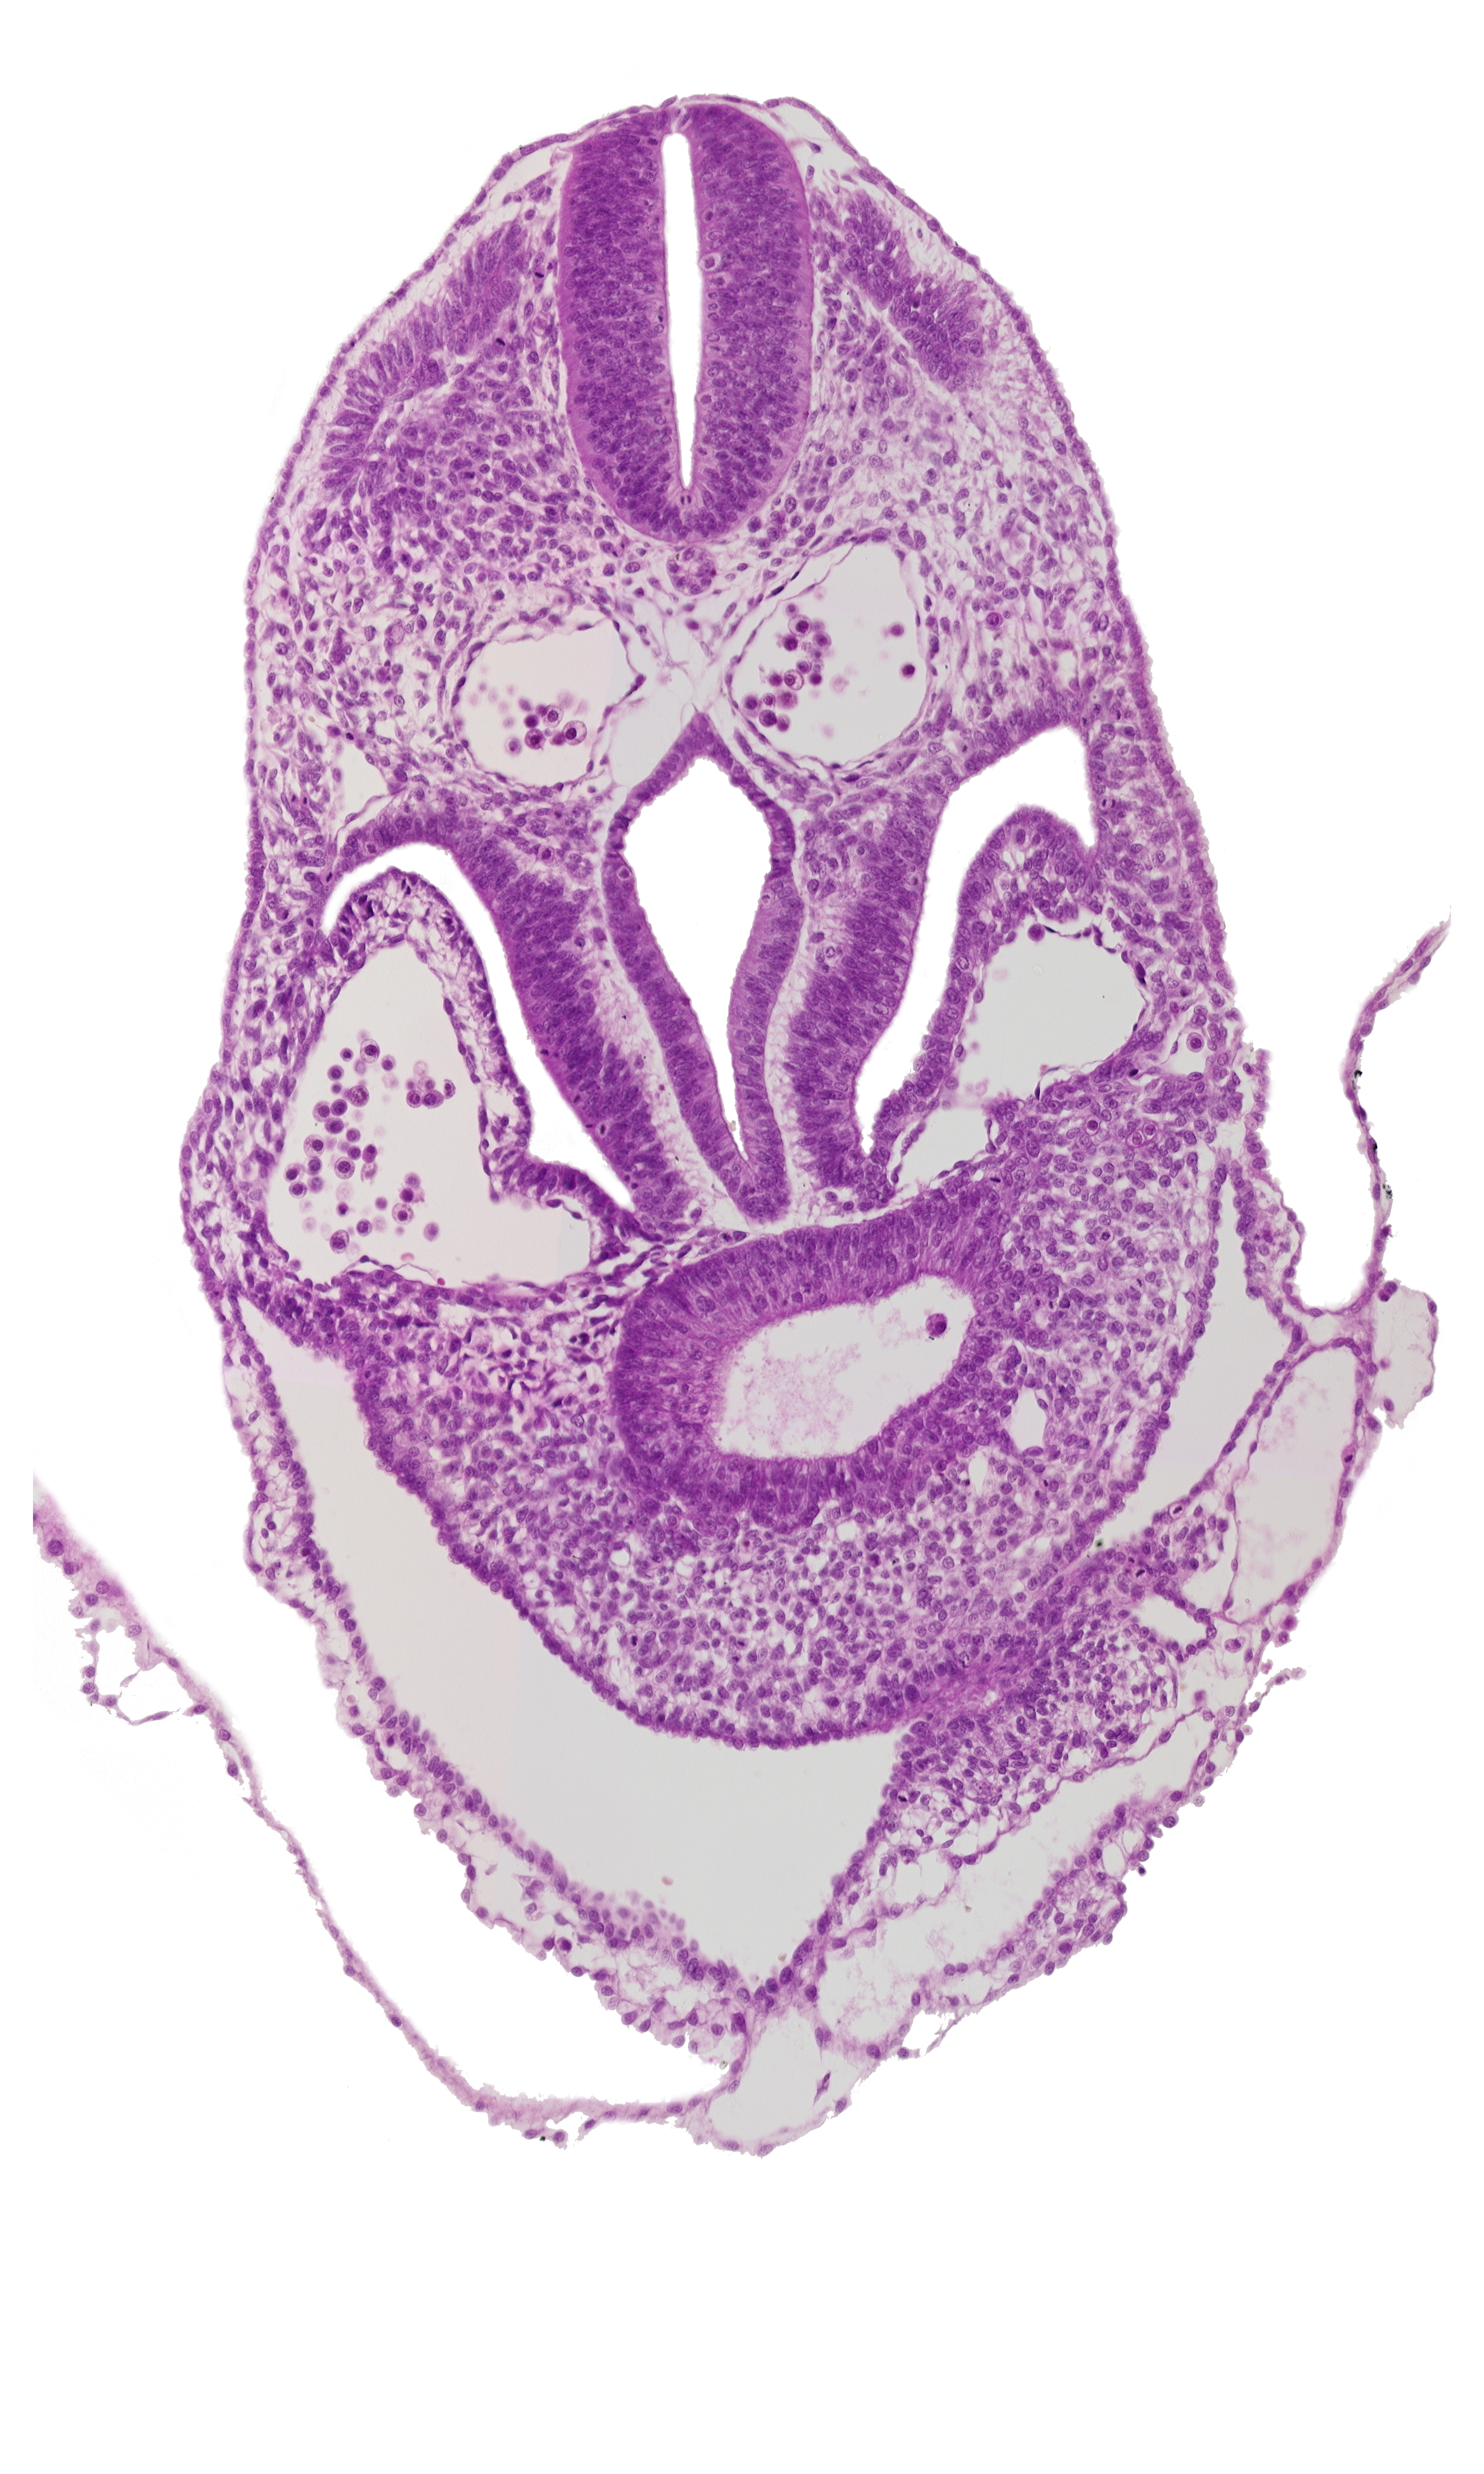

Carnegie Embryo #8943 | Location: 05-02-02

Keywords: amnion, amniotic cavity, dermatomyotome 5-6 interspace, hepatic antrum, junction of amnion and ventral body wall (caudal part of head), pericardial cavity, pericardioperitoneal canal (pleural cavity), postcardinal vein, septum transversum

Source: The Virtual Human Embryo.